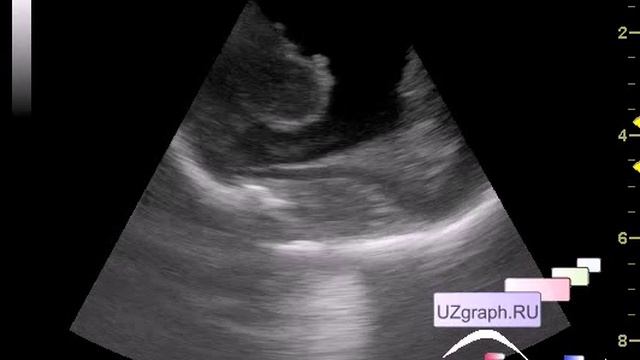

Постгеморрагическая гидроцефалия, внутрижелудочковое кровоизлияение - видео

Недоношенный новорожденный в реанимации, назначено #УЗИ головного мозга (НСГ). Подробнее: ,